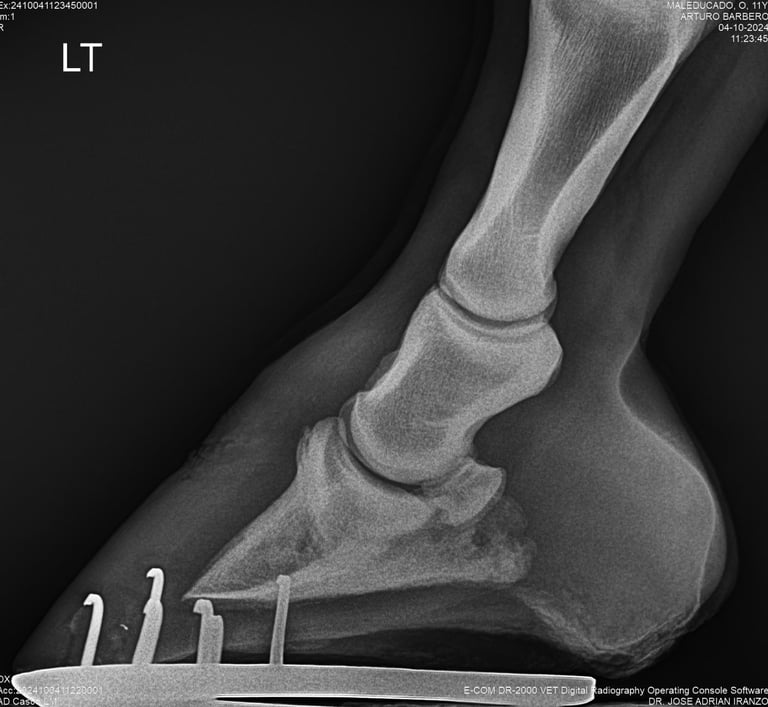

DIAGNOSTICO POR IMAGENES: ECOGRAFIA Y RADIOGRAFIA